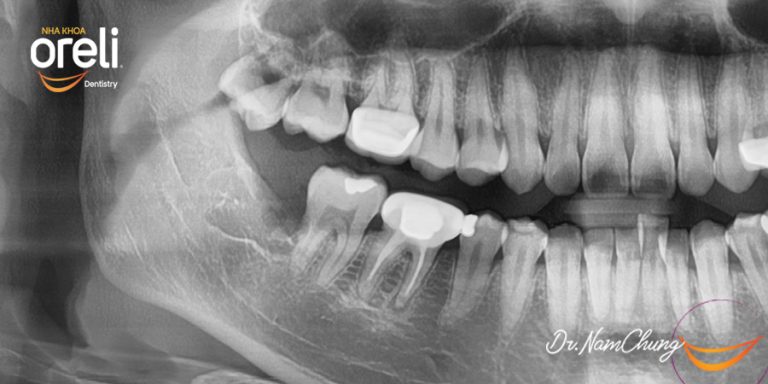

Nhổ răng khôn hàm dưới mọc lệch – Ca thực tế tại Oreli Buôn Ma Thuột

Nhổ răng khôn

Mọc lệch

Xem thêm